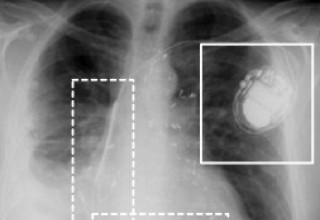

Ransomware and stolen PHI are just the tip of the iceberg when it comes to cyberattacks in healthcare. The growing number of vulnerable networked medical devices, from pacemakers to MRI Systems, is great cause for alarm.

Hacked medical devices could be the next big security nightmare. There are currently between 10 and 15 connected devices per hospital bed in the United States, many of which are vulnerable to attack. Anything that connects wirelessly to other equipment can be compromised, with historically low levels of security on medical instruments and embedded devices already linked to a number of security attacks. Learn more about Hacked Medical Devices.

"Ransomware and stolen PHI are just the tip of the iceberg when it comes to cyberattacks in healthcare. The growing number of vulnerable networked medical devices, from pacemakers to MRI Systems, is great cause for alarm," stated Christian Espinosa, CEO, Alpine Security.